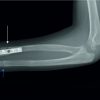

A 56-year-old man sustained a traumatic amputation at the mid-calf combined with dislocation of the proximal tibiofibular joint and rupture of the posterior cruciate ligament. His tibiofibular joint was stabilized which provided enough knee stability for rehabilitation and eventual full activity as a motorcycle mechanic using a vacuum assisted suspension system (VASS) socket with a hydraulic foot and ankle. Over the next 2 years, heavy labor saw a progression of underlying knee osteoarthritis which significantly affected his ability to work and mobilize. Plain films revealed predominantly patellofemoral joint (PFJ) osteoarthritis with some degenerative changes also seen in both medial and lateral compartments (Fig. 1). Prosthetic adjustment was not effective in offloading the PFJ and given his increasing pain, recurrent hemarthroses and inability to perform heavy work it was decided to proceed to a TKA. Patient consent and local ethics committee approval were obtained (NSLHD HREC RESP/17/110).

Post-operative radiographs reveal an unexpected proximal tibial cut in varus alignment (Fig. 4). Stump swelling had settled by 6 weeks and was sufficiently stable enough to allow fitting with a new prosthesis at 8 weeks. The new VASS socket fitting resulted in neutral functional coronal alignment and a range of motion from 0° to 110° of flexion (Fig. 5). The patient returned to full manual duties in his job as a motorcycle mechanic 2 weeks after prosthesis fitting and 10 weeks after surgery. At 1-year follow-up, the Oxford Knee Score improved from 32 to 42, the Veterans Rand 12 Item Health Survey (VR-12) physical score from 38.6 to 42.9 and the mental score from 42.2 to 48.8. In a patient satisfaction questionnaire, he described very good relief of pain, and very good ability to perform heavy manual labor including squatting and lifting.

There have been a number of reports of a successful TKA in the presence of various different levels of ipsilateral below knee amputation [3,4,5,6,7,8,9]. Authors describe different methods of overcoming the challenges they faced. It has been demonstrated that the weight bearing load which is distributed by the VASS from the prosthesis to the stump concentrates the highest stump pressures during the gait cycle onto the lateral cortex of the tibia [10]. Therefore, when viewing the stump to guide alignment, the center of the most distal aspect should be at the far lateral aspect of the shaft of the tibia. Radiographic varus tibial alignment is a potential consequence of this and this is where the tibial component was aligned in this case (Fig. 6a). If an intra-operative radiograph had been performed and alignment matched to the tibial shaft, overall functional alignment may not have been correct. In addition, increased bone density can be seen laterally as a potential response to the load with this alignment (Fig. 6b). Radiographic evidence of a tibial cut in varus alignment appears to be commonly seen. Crawford and Colman described using a sterile box to hold the stump with the knee fully flexed and supported throughout by an assistant. They used an intramedullary rod to gain tibial alignment with post-operative radiographs similar to our result with varus tibial alignment. Clinical review at 8 months revealed good function [4]. Amanatullah et al. presented 13 TKA cases; however, only one was in the ipsilateral knee. Surgical technique is not described but they state component positioning as a serious issue because of the loss of anatomic landmarks and their post-operative radiograph also shows varus alignment [5]. Konstantakos et al. described the use of a plaster mold of the stump to create a modified prosthesis which was sterilized and enabled intraoperative alignment when paired with an extramedullary tibial jig. While complex, post-operative radiographs show that with this setup they achieved neutral alignment [6]. This was also achieved by Dudhniwala et al. who reported sequential TKAs on a patient with bilateral fibular deficiency. Due to a long residual tibial stump, an intramedullary alignment rod and long stemmed primary components were used [7]. A novel approach was adopted by Fleming and Dixon [8] who performed a TKA for a patient with progressive arthritis who 17 years earlier had received a below-knee amputation. They were faced with a very short, truncated valgus tibia, and opted to use custom computer generated cutting guides. Pre-operative computerized tomography images were taken while the prosthetic leg was worn to determine the mechanical axis. Post-operative radiographic alignment was not evaluated but functional outcome was reported as excellent. In our case, the prosthesis could not be fitted reliably onto the stump until 8 weeks postoperatively due to swelling. Pasquina and Dahl [9] reported the use of a modified prosthesis which was fitted preoperatively and casted over 12-ply stockings to accommodate the anticipated post-operative edema and allow immediate postoperative training and full weight bearing by day 4 and final prosthesis fitting was achieved at 6 weeks. Dudhniwala et al. [7] managed prosthetic leg fitting at 6 weeks after an initial period of non-weight bearing and wheelchair use.